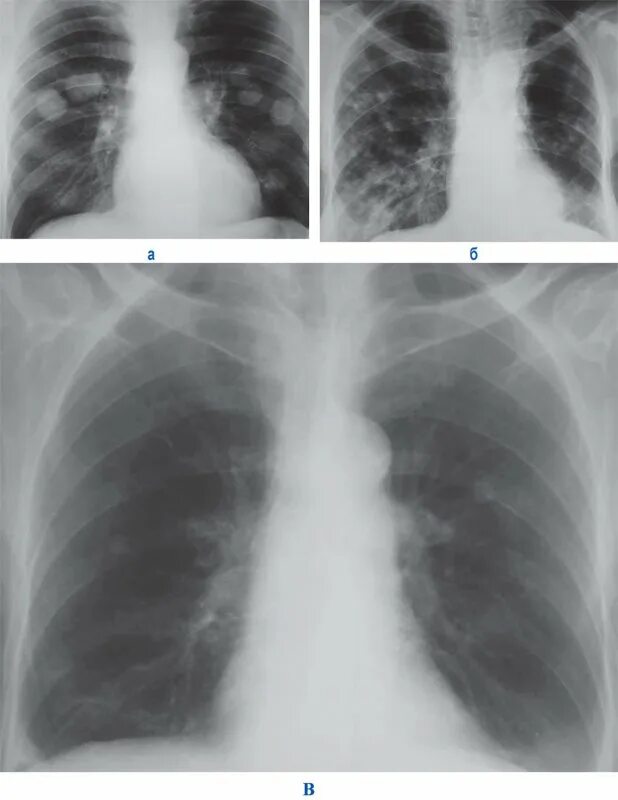

Метастазы в легких терапия